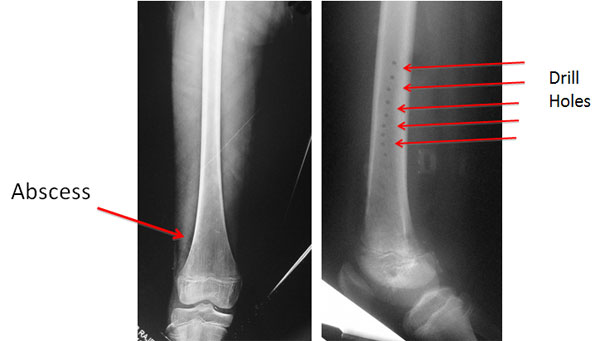

| Acute Osteomyelitis – Infection of the bone and medullary cavity is common in young children in the age group of 3-14 years. The infection presents as severe pain in the affected limb and high grade fever. This young girl of 12 years was diagnosed as acute osteomyelitis. She was treated somewhere else with I&D and Multiple drill holes. |

| The infection persisted and there is formation of new bone (Involucrum) around the dead necrotic bone (Sequestrum). |